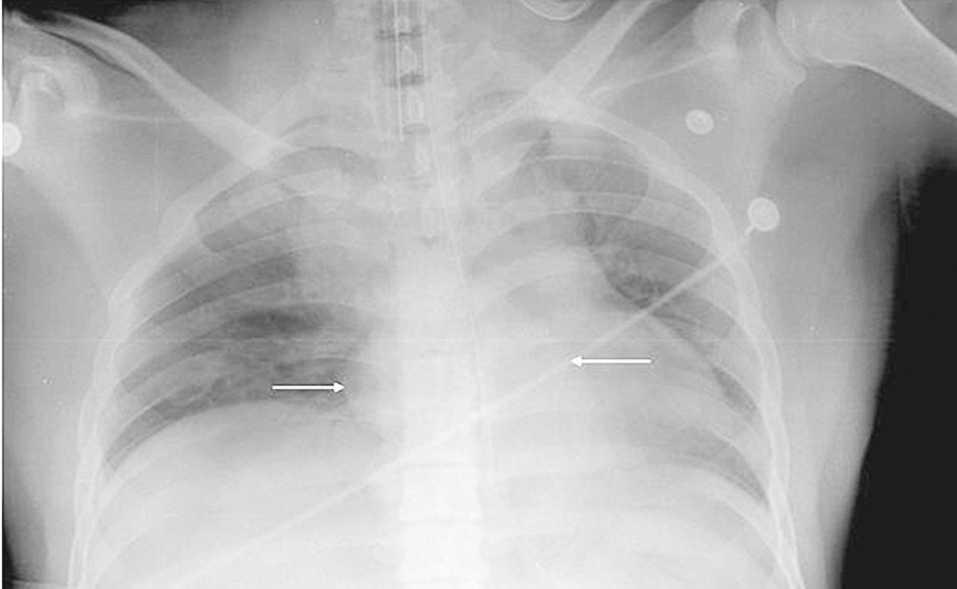

Varón de 23 años trasladado a nuestro hospital por el servicio de emergencias extrahospitalarias en situación de parada cardiorrespiratoria no recuperada tras protocolo de reanimación cardiopulmonar avanzada, por lo que se activa código de donante en asistolia, mientras se mantiene el masaje cardíaco con ventilación mecánica y se conecta al paciente a circulación extracorpórea. En la radiografía de tórax que se realiza en el proceso de validación pulmonar se evidencia masa mediastínica radioopaca de localización inferior y media. Se aprecian signos de broncoaspirado, por lo que se desestima la extracción pulmonar. Las pruebas de tóxicos en orina detectan cocaína, por lo que se descarta al paciente como donante. La autopsia confirma que hay paquetes de cocaína a distintos niveles del tubo digestivo, entre ellos el tercio distal del esófago. Uno de los paquetes tenía una rotura del envoltorio, lo que permitió la absorción masiva de cocaína que causó la parada cardíaca.

Fig. 1.

Diagnóstico: muerte súbita de paciente con masa mediastínica.